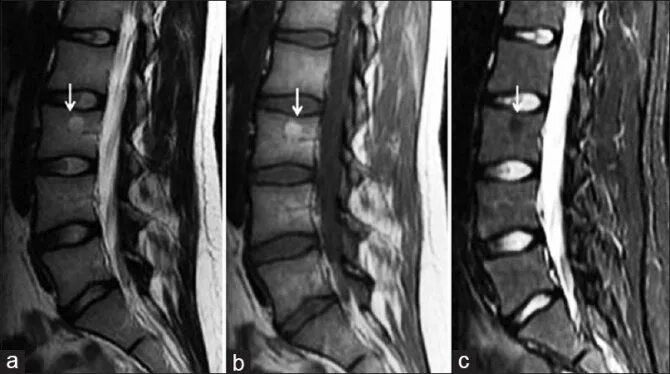

Изменения по типу modic